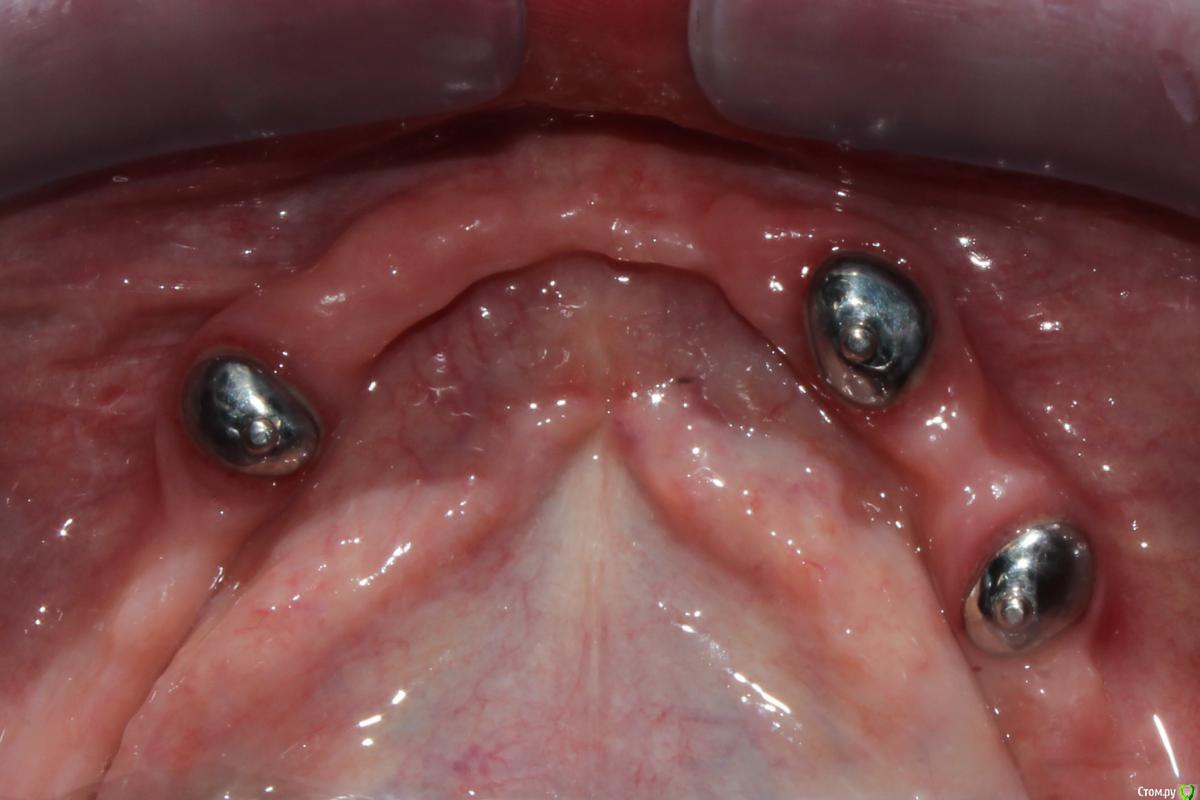

dr.Dre Опубликовано 1 февраля, 2016 Поделиться Опубликовано 1 февраля, 2016 Добрый день что это за система фиксации съёмников ? Ссылка на комментарий

Stomka Опубликовано 1 февраля, 2016 Поделиться Опубликовано 1 февраля, 2016 (изменено) я знаю, что это называется супрарадикулярный аттачмент.. по моему не тянет на громкое слово "система" Изменено 1 февраля, 2016 пользователем Stomka Ссылка на комментарий

anvladd Опубликовано 1 февраля, 2016 Поделиться Опубликовано 1 февраля, 2016 насколько надежны такие аттачменты? не повылетают из корней? Ссылка на комментарий

Дмитрий171 Опубликовано 1 февраля, 2016 Поделиться Опубликовано 1 февраля, 2016 СИЦ держит плохо. Фиксирую адгезивно на композитный цемент Ссылка на комментарий

Larnary Опубликовано 1 февраля, 2016 Поделиться Опубликовано 1 февраля, 2016 (изменено) Обычные Бреденты(или аналог) на вкладках. Реализация идеи ненадежная. Что касается протеза на нижнюю челюсть.Правильнее было бы сделать в протезе литую балку и вставить в нее матрицы. Изменено 1 февраля, 2016 пользователем Larnary Ссылка на комментарий

Doc Опубликовано 1 февраля, 2016 Поделиться Опубликовано 1 февраля, 2016 Прямо ностальгия замучала. ))Мы такие вкладки с шариками делали еще в прошлом веке в платной поликлинике. )) Надо же, еще живы. Кстати, парочка пациентов с этим по сей день ходит. 2 Ссылка на комментарий

Ronin Опубликовано 1 февраля, 2016 Поделиться Опубликовано 1 февраля, 2016 У меня это просто культевые аттачменты по типу бредента, как упомянули ранее)) иногда приходится делать, когда финансы не позволяют разгуляться на другие виды конструкций или в свете атрофии и сопутствуещей патологии.. Зато лучше, чем просто съемник при диабете или частичный. А по поводу фиксации самих замков, то как вкладки, если нормально ставить, соблюдая протокол, то ничего не вылетает))) Ссылка на комментарий